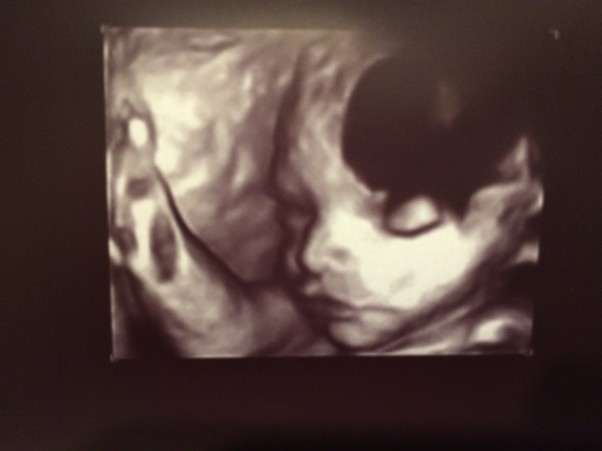

Dziś znów byłam u lekarza. Eliza leży główką w dół, waży ok 1500g, wszystko jest w jak najlepszym porządku jak na 29 tydzień. No i w końcu dała się trochę podejrzeć, choć lekarz mówił, że mogłaby bardziej "na nas" patrzeć.